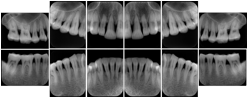

OO.1.4 Radiology

• A radiologist on his PACS assembles a screen layout of a stack of CT images of a current lung study, a secondary capture of a 3-D rendering of the CT, and a prior chest radiograph for the patient. He adjusts the window width / window level for the CT images, and zooms and annotates the radiograph to clearly indicate the tumor. He saves a Structured Display object representing that screen layout, including Grayscale Softcopy Presentation State objects for the CT WW/WL and the radiograph zoom and annotation. During the weekly radiology department conference, on an independent (non-PACS) workstation, he accesses the Structured Display object, and the display workstation automatically loads and places the images on the display, and presents them with the recorded WW/WL, zoom settings, and annotations.

• A mammographer reviews a screening exam on a mammo workstation. She wishes to discuss the exam with the patient's general practitioner, who does not have a mammo-specific workstation. She saves a structured display, with presentation states for each image that replicate the display rendered by the mammo workstation (scaling, horizontal and vertical alignment, view and laterality annotation, etc.).

Mammography Structured Display

Figure OO-7. Mammography Structured Display